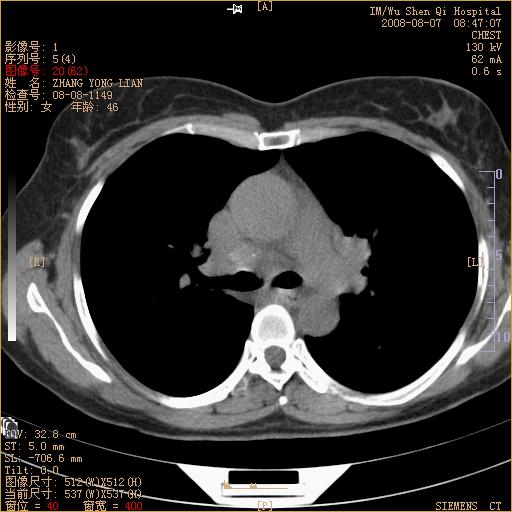

标题: CT15050:女,46岁,咳嗽胸痛一月余 [打印本页]

标题: CT15050:女,46岁,咳嗽胸痛一月余

纵隔窗没发全,左下肺近胸膜处结节。有长毛刺,纵隔淋巴结增大,不排除恶性病变。

考虑肺癌

考虑左肺下叶后基底段周围型肺癌伴纵隔淋巴结转移可能性大。

左下肺ca并纵隔及左肺门区淋巴结转移。

脾脏低密度结节转移不排除。

1)考虑左肺下叶后基底段周围型肺癌伴纵隔淋巴结转移。2)脾内低密度灶,性质待定;不排除转移瘤可能。

考虑左肺下叶后基底段周围型肺癌伴纵隔及肺门淋巴转移。